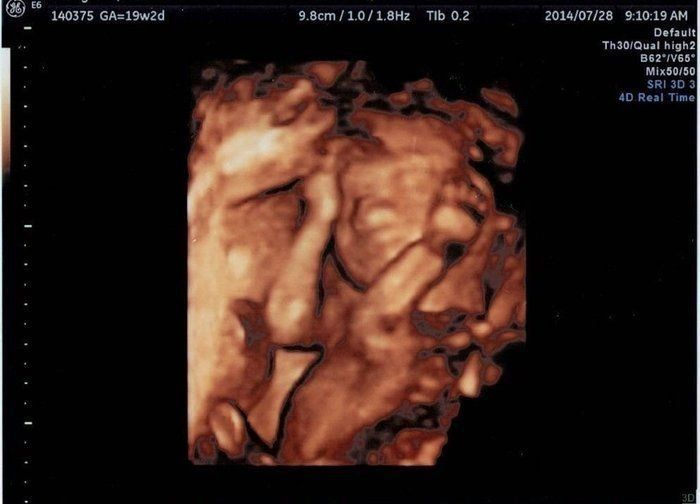

こぢんまり子さんの妊娠19週目のエコー写真 性別判明、女の子でした

このエコー、わかりにくいかも知れませんが、太ももとお股だけの画像です。右側がお股、そこから左に向かって2本の足が伸びています。太ももから先は、写っていない状態。性別が分かる頃なので、そのあたりを中心にエコーを写してくれました。お股に何もないので、女の子ですねと言われました。この頃、戌の日のお参りに行き、安産で無事に生まれますようにとお願いしました。